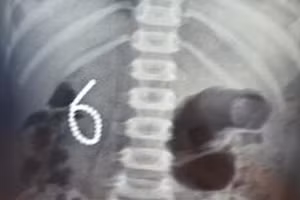

GD&TĐ - Vừa qua, Khoa Ngoại Tổng H ợp – Bệnh viện Nhi Thanh Hóa vừa phẫu thuật thành công ca bệnh dị vật đường tiêu hóa cháu Đ.N.D.A (04 tuổi), ở huyện Nông Cống, tỉnh Thanh Hóa.

GD&TĐ - Từ phim chụp X-quang các bác sĩ dự đoán có khoảng 25-30 viên nam châm trong bụng cậu bé, nhưng khi cậu bé thực sự bước ra khỏi cuộc phẫu thuật, họ nói rằng có 54 viên nam châm trong bụng.